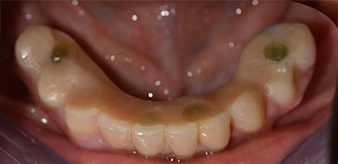

La paziente, 64 anni, presenta una dentatura residua di denti 38, 33 e 43 e una protesi combinata innestata nella mandibola (Fig. 1 e 2).

dentatura residua

Fig. 1

Fig. 2